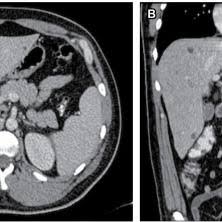

Sindrome De Caroli En Imagenes A Proposito De Un Caso

Sindrome De Caroli En Imagenes A Proposito De Un Caso from scielo.isciii.es. Para más información pulse aquí para ir al website.